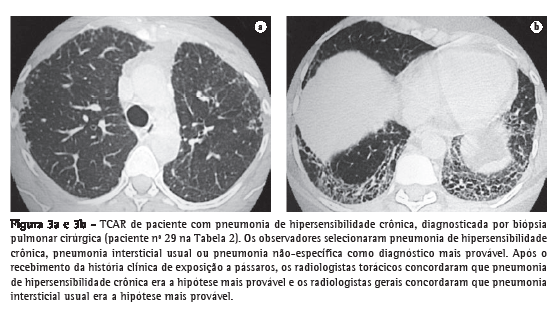

Os dois radiologistas torácicos concordaram quanto ao diagnóstico mais provável para cada paciente em 48,3% (κ = 0,42) e 62,1% (κ = 0,58) dos casos, respectivamente, antes e após o recebimento das informações clínicas. Os dois radiologistas gerais concordaram quanto ao diagnóstico mais provável para cada paciente em 37,9% (κ = 0,32) e 36,2% (κ = 0,30) dos casos, respectivamente, antes e após o recebimento das informações clínicas (Figuras 1-3).